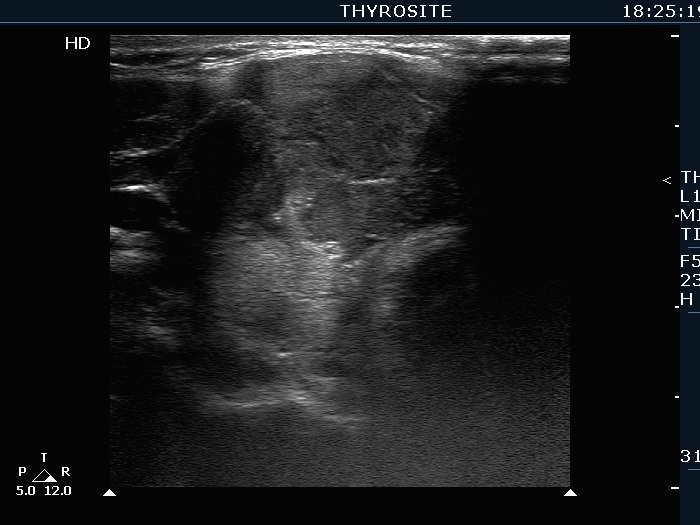

Extrathyroidal spread - case 2113 (ultrasonographic picture 2)

Right lobe, another transverse scan. If we consider the ventral wall of the trachea, it is evident that great proportion of the mass is located ventral to the normal position of the thyroid. It means that the tumor presents bulging of extreme degree.